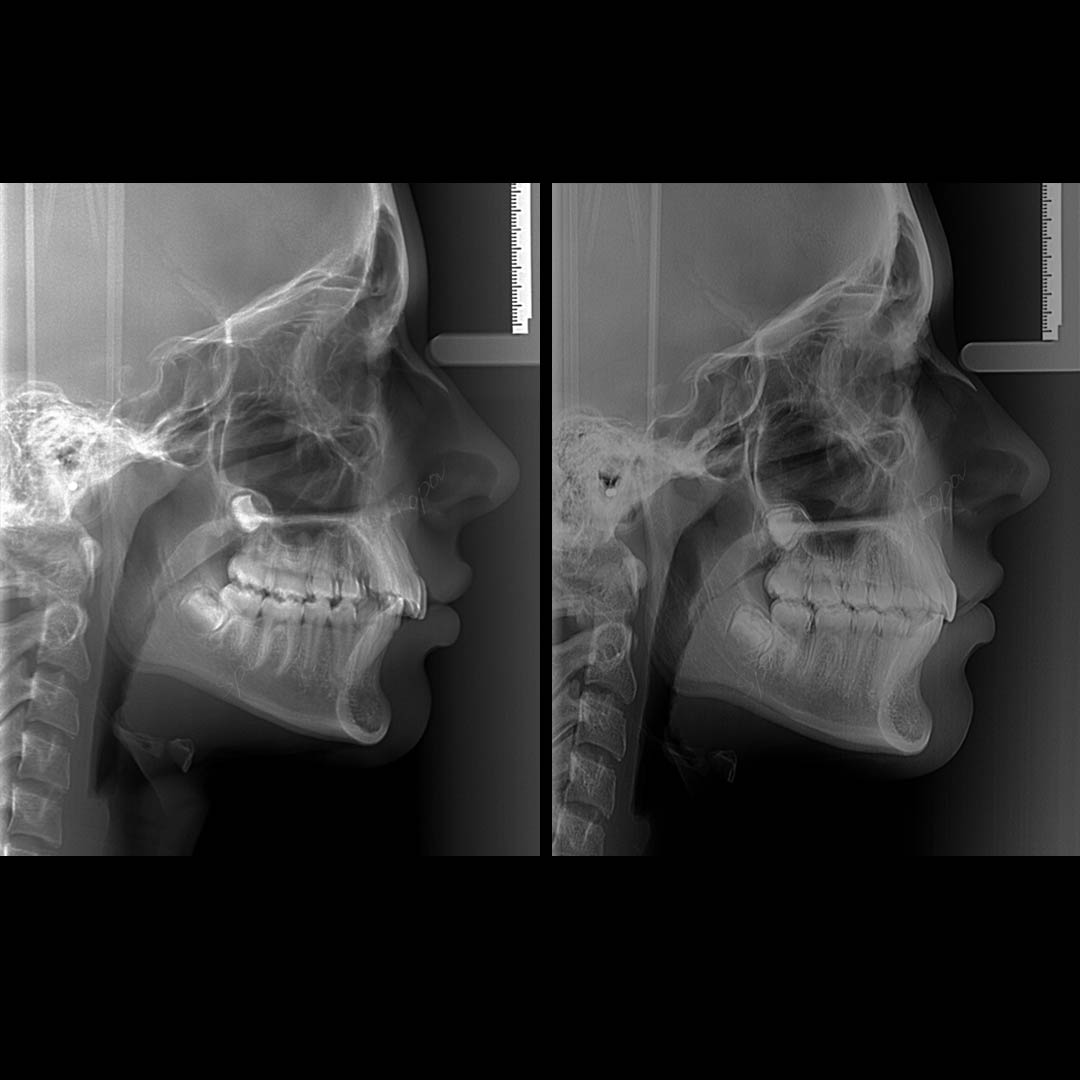

Distalan zadrižaj je često udružen sa dubokim sadržajem.

Lice ima konveksan profil sa naglašenim sulfiksima.

Pravovremena terapija i otklanjanje uzroka daje odlične dugotrajne rezultate u kratkom vremenskom periodu.

U ovom slčaju terapiju smo sproveli fiksnim aparatima, a uz pomoć dodatnih aparata smo korigovali dubok zagrižaj i prinudu koja je bila uzrok distalnog zagrižaja.

Ukupno vreme terapije 13 meseci.